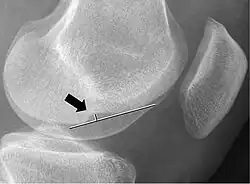

Deep lateral femoral notch sign

In radiology, the deep lateral femoral notch sign is a finding on a lateral radiograph that is considered an indirect sign of a torn anterior cruciate ligament (ACL).[1][2] It is an abnormal deepening of the lateral condylopatellar sulcus from an osteochondral impaction fracture.[1][3] A depth greater than 1.5 mm (0.059 in) is a reliable sign of a torn ACL.[1]